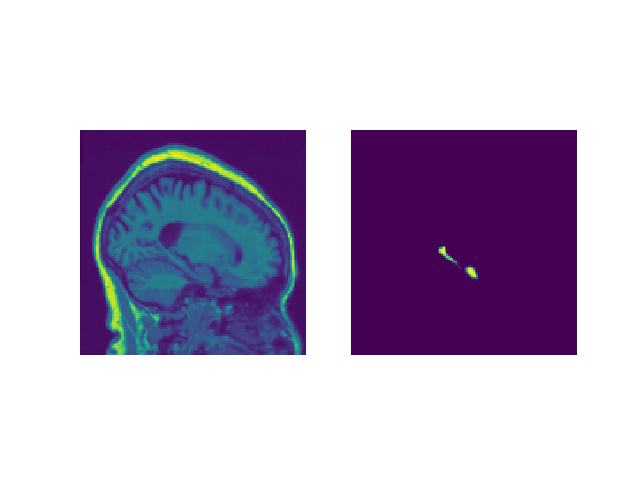

Schichtvisulisierung

Eingabebildvisulisierung zur Überprüfung

a) Originalbild

Würfelbewertung für Hippocampus-Segmentierung ADNI-LONI-Datensatz